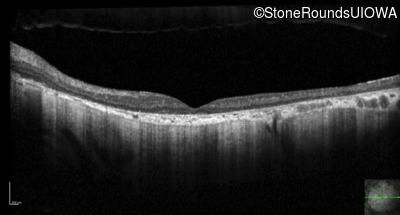

Optical Coherence Tomography - Left - 10/125 sc

Exemplar / OCT Stack

OCT Stack